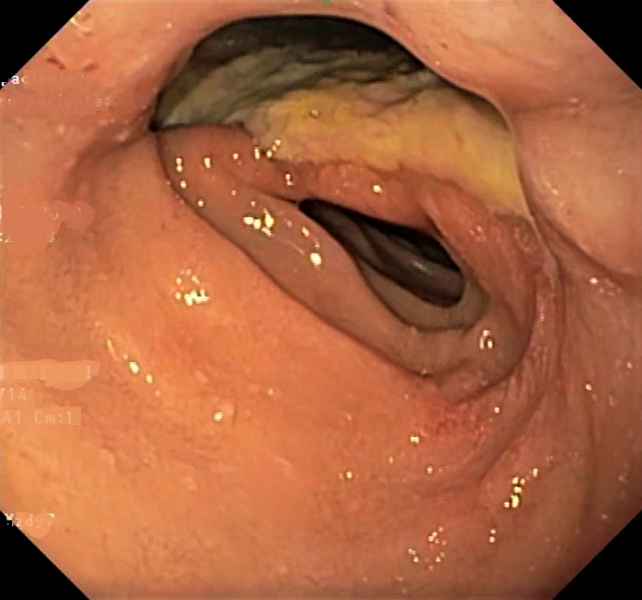

A plausible case of sloughing esophagitis